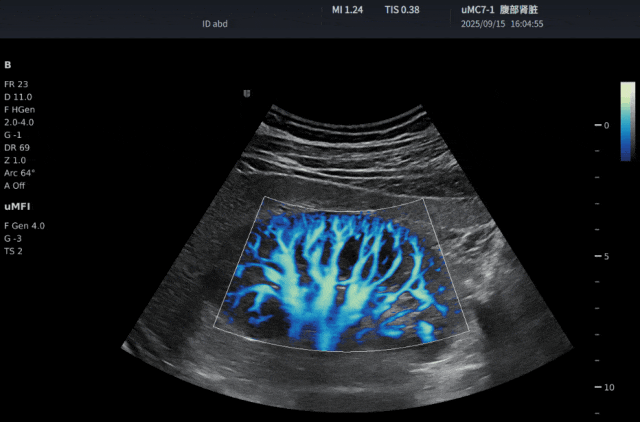

SensiFlow 超敏血流技术

在超声临床上,准确的观测病变周围的血流信息是医生判断病变情况的重要方法之一。而往往使用超声血流技术做检查时,都会受到低速血流不敏感、高速血流信号混叠和血流噪声大的困扰,医生们在使用超声血流技术做检查时希望看到更细微、更低速、更稳定、更干净、血流形态更好的血流信号,联影提供的 SensiFlow 超敏血流技术就很好的满足了这个需求。

SensiFlow 超敏血流技术采用四大核心处理链路,赋能超敏生动血流。通过时频分析技术高效去除组织信号;通过特征空间分析技术精准识别真实血流;通过实时运动伪像抑制机制保证稳定成像;通过血流动力学模型有效提升血流形态。提供了能达到类造影效果的微血流信号。可以检出百微米微小血管,并且真实连贯的显示出血流形态。

相较于目前市面上大多数的超声机器只能看清肾脏的三级血管,联影的超声的血流技术肾脏可以在此基础上清晰呈现肾脏四级血管的血流信号;其他机器束手无策的肠管、胆囊息肉和肿瘤微弱新生血管等微细血管对联影超声来说也不算挑战。